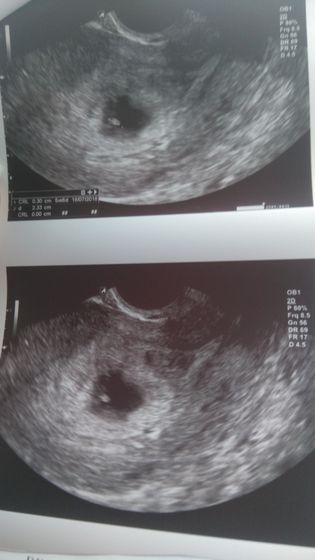

Есть и желточный мешочек, и плодное яйцо не 2мм, а до 22 мм.

Даже увидела своего малыша ?

Единственное, что срок по УЗИ получается не 7 недель, а 6 недель.

Врач, поддержал, сказал что здесь все развивается.

Внизу можете посмотреть и заключение и снимок.